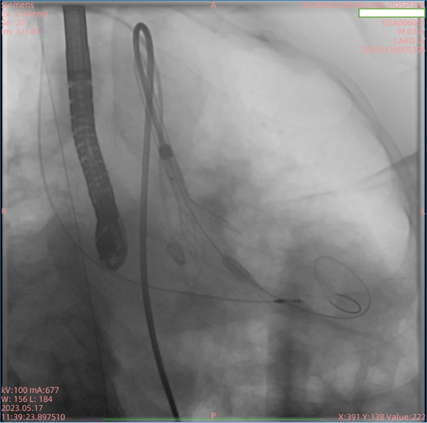

患者为74岁男性,因“反复胸闷1年余,加重1周”入住我院心内科病房。入院后完善心脏彩超,根据结果诊断为主动脉瓣重度狭窄。此次手术选用园区某生物医药公司自研的瓣膜,术前跨瓣压差测得68mmHg左右,术后即刻跨瓣压差小于5mmHg,手术效果较好。